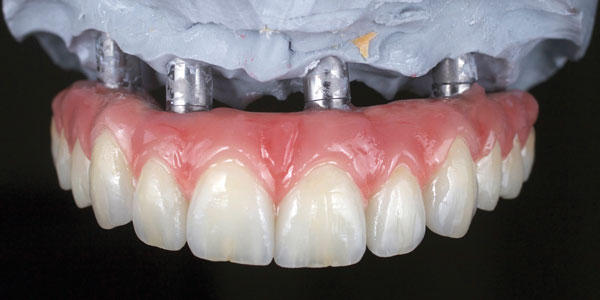

Implant/ Surgery

Prosthodontics